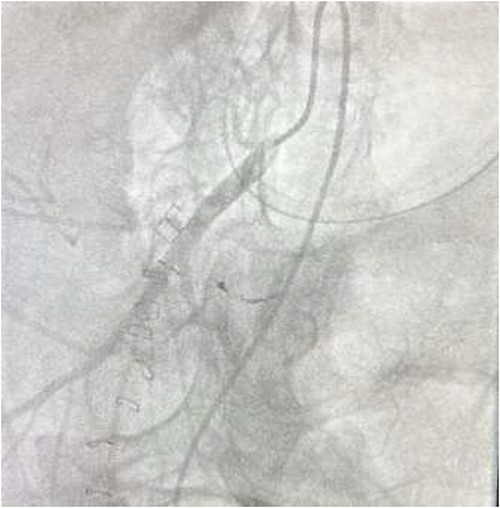

CTA demonstrated angiodysplasia in the duodenal diverticulum at the duodenojejunal junction with associated contrast blush (Figs 1 and 2). The urgent opinion of an interventional radiologist was sought in a tertiary centre. The patient was accepted for urgent embolization in an attempt to stabilize the patient. The patient required an intra-hospital transfer overnight.

The on-call interventional radiology team performed a successful embolization. A 6-French Sheath was passed through the left common femoral artery, and a 5-French Sim-1 catheter was advanced into the coeliac and common hepatic artery. A 2.4 French Direxon microcatheter was advanced into a branch of the superior mesenteric artery at the site of bleeding. Successful coil embolization with a 2 mm × 2 mm concerto micro coil was performed. A satisfactory angiographic result with DYNA-CT, also known as modern C-arm CT or cone-beam CTA, showed no extravasation.

There were no immediate complications to the procedure. The patient returned to intensive care post-operatively. He remained intubated and vital laboratory tests were stabilized. He experienced acute renal failure post-procedure that required haemodialysis and prolonged intubation (Figs 3 and 4).